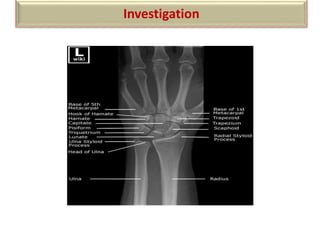

Investigation

X-RAY